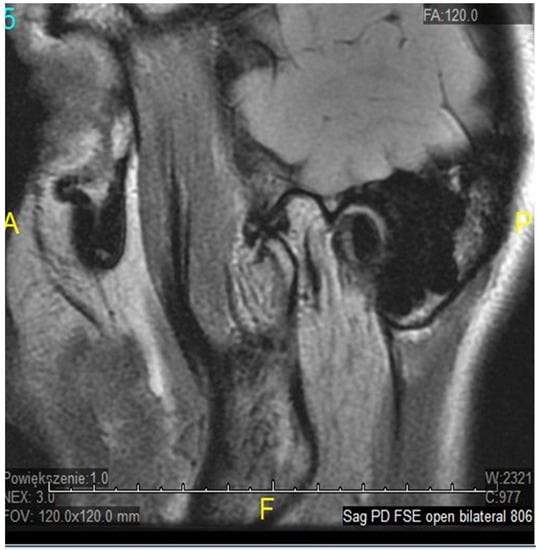

- Litko-Rola, M.; Szkutnik, J.; Różyło-Kalinowska, I. The importance of multisection sagittal and coronal magnetic resonance imaging evaluation in the assessment of temporomandibular joint disc position. Clin. Oral Investig. 2021, 25, 159–168. [Google Scholar] [CrossRef]